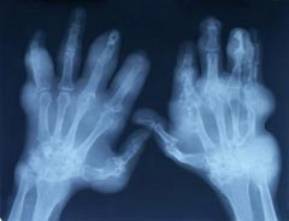

- Radiografía

de la articulación que puede estar normal